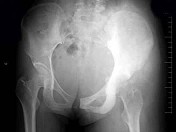

- 单项选择题女,16岁, 左臀部疼痛伴发热2个月,摄片如图所示, 最可能的诊断是 ( )

A、左髂骨成骨肉瘤

B、左髂骨急性化脓性骨髓炎

C、左髂骨软骨肉瘤

D、左髂骨网状细胞肉瘤

E、以上均不正确